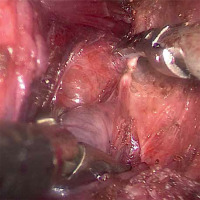

Under single-port endoscopy with carbon dioxide insufflation, the thyroid lobe is retracted medially with a laparoscopic grasper, then the plane between the thyroid and carotid artery is opened. The middle thyroid vein, if present, is divided with the ultrasonic scalpel. The superior pole is pulled inferiorly, and the avascular space between the superior pole and the cricothyroid muscle is opened to expose the branches of the superior thyroid artery and vein, which are transected as closely as possible to the gland to avoid injuring the external branch of the superior laryngeal nerve (Photo 3). Then the superior pole is freed up from its remaining attachments and mobilized inferiorly. The superior parathyroid gland is often identified clearly on the posterior aspect of the superior pole; however, if it is not seen clearly, it is unnecessary to perform further dissection provided that the dissection is kept to the thyroid capsular plane. Attention is redirected to the inferior pole. The inferior thyroid vein is divided close to the thyroid gland. The thyroid lobe is then rolled medially, and the perithyroidal tissue is carefully dissected. The recurrent laryngeal nerve is then identified, usually in the tracheoesophageal groove (Photo 4). The nerve is then traced for a distance of approximately 2 to 3 cm. The inferior parathyroid gland may be encountered and identified during the inferior pole mobilization.

Photo 4

Exposure of the recurrent laryngeal nerve (white arrow) and identification of the inferior parathyroid gland (black arrow)